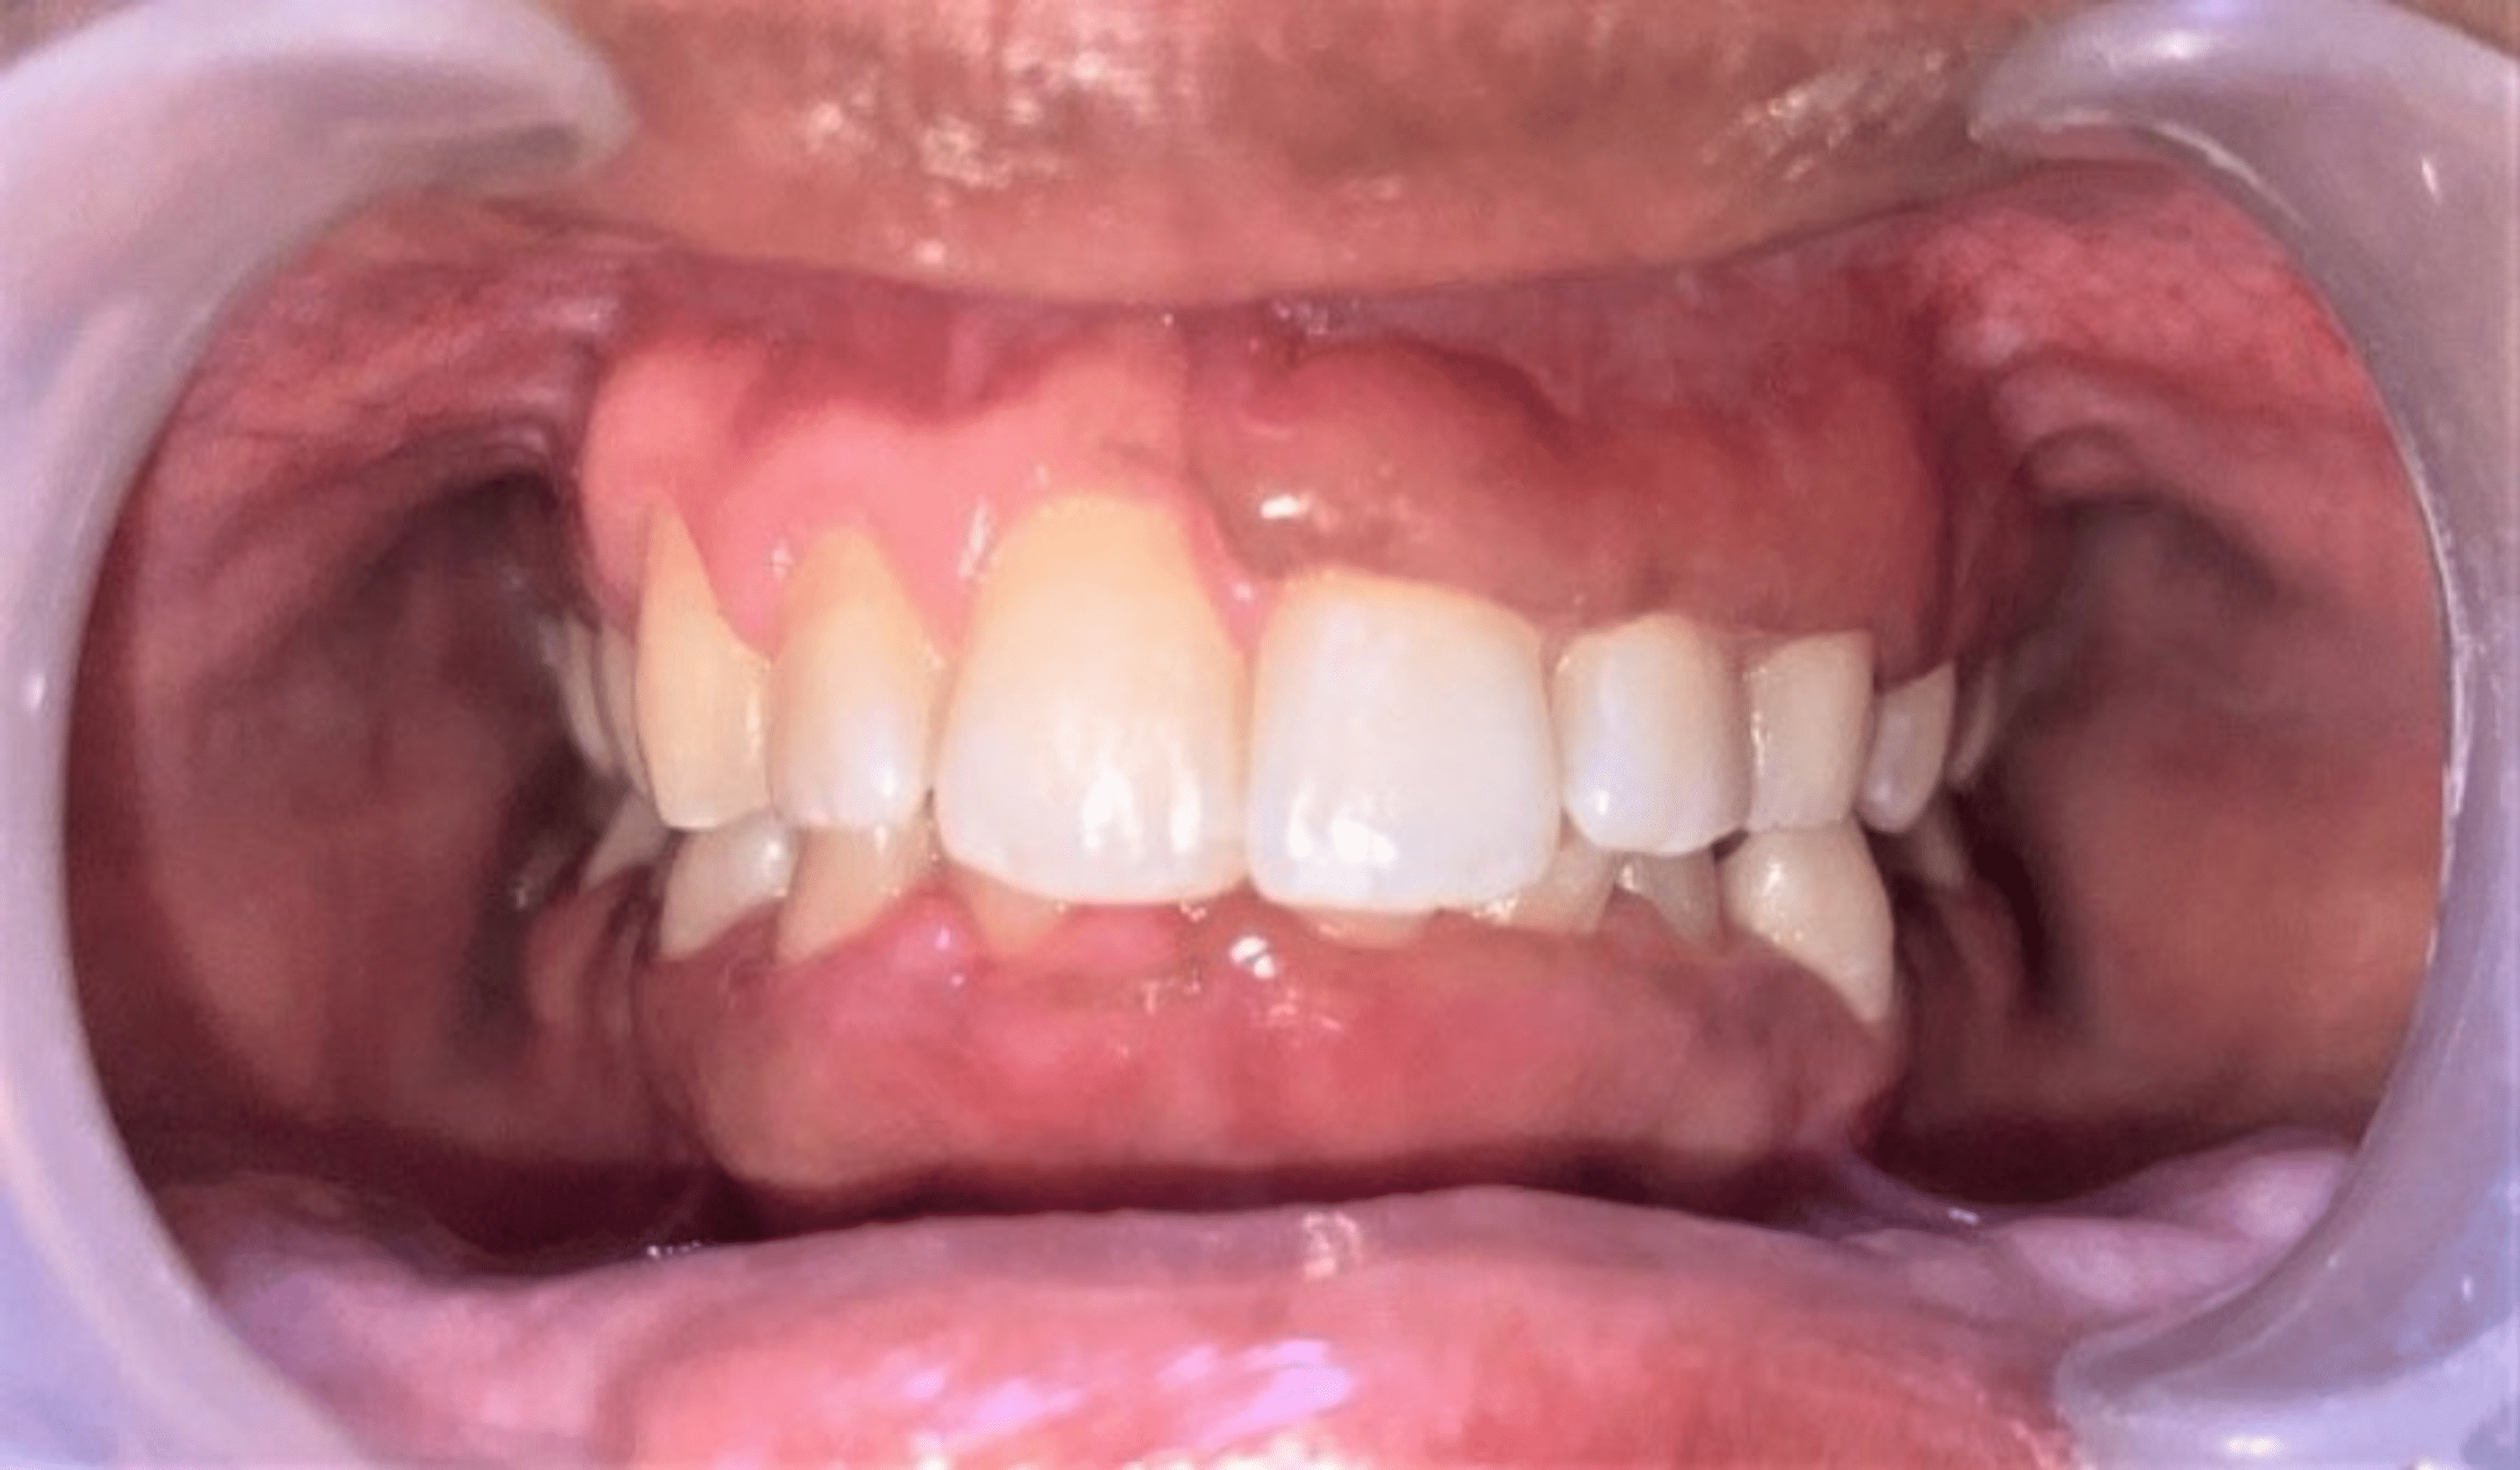

Vitamin C Deficiency Gingival Enlargement . In the present case report, we note that mild vitamin c deficiency associated with metabolic syndrome and severe periodontal infection is a. Provides overview of possible aetiology of gingival overgrowth. Discusses history and key clinical features which aid in diagnosis. Vitamin c deficiency/scurvy was initially associated with sailors who undertook. Dietary advice or supplements may be necessary to treat vitamin c deficiency. It has been suggested that vitamin c deficiency/scurvy is associated with gingival inflammatory changes; Gingival enlargement (ge) is a clinical condition of an increase in the size of the gingiva and a very common feature of gingival and periodontal. The conditioned gingival enlargements are usually associated with hormonal changes (pregnancy, puberty), nutritional deficiency (vitamin c deficiency), allergic (plasma. Granulomatous diseases require specialist medical input and if suspected, referral should be. The intervention using vitamin c administration improved gingival bleeding in gingivitis, but not in periodontitis.

Gingival overgrowth caused by vitamin C deficiency associated with Vitamin C Deficiency Gingival Enlargement The conditioned gingival enlargements are usually associated with hormonal changes (pregnancy, puberty), nutritional deficiency (vitamin c deficiency), allergic (plasma. The intervention using vitamin c administration improved gingival bleeding in gingivitis, but not in periodontitis. Provides overview of possible aetiology of gingival overgrowth. Dietary advice or supplements may be necessary to treat vitamin c deficiency. Discusses history and key clinical features. Vitamin C Deficiency Gingival Enlargement.

Gingival overgrowth caused by vitamin C deficiency associated with Vitamin C Deficiency Gingival Enlargement The intervention using vitamin c administration improved gingival bleeding in gingivitis, but not in periodontitis. Dietary advice or supplements may be necessary to treat vitamin c deficiency. Gingival enlargement (ge) is a clinical condition of an increase in the size of the gingiva and a very common feature of gingival and periodontal. In the present case report, we note that. Vitamin C Deficiency Gingival Enlargement.

Gingival overgrowth caused by vitamin C deficiency associated with Vitamin C Deficiency Gingival Enlargement The intervention using vitamin c administration improved gingival bleeding in gingivitis, but not in periodontitis. Discusses history and key clinical features which aid in diagnosis. In the present case report, we note that mild vitamin c deficiency associated with metabolic syndrome and severe periodontal infection is a. Provides overview of possible aetiology of gingival overgrowth. Vitamin c deficiency/scurvy was initially. Vitamin C Deficiency Gingival Enlargement.